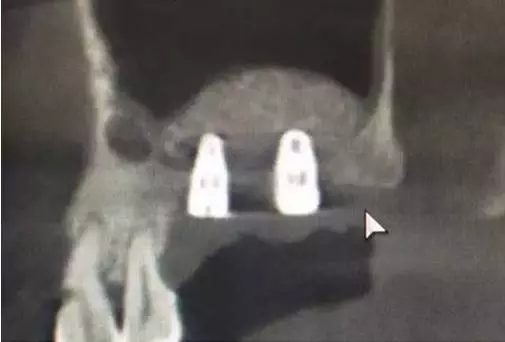

植入兩顆植體。

術(shù)后6,7牙位CT片,顯示充足的植骨量。

整個手術(shù)時間僅20分鐘,充分體現(xiàn)了:安全、方便、快捷的原則。